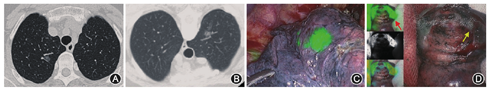

术中所有患者均可见荧光显像,前两例患者ICG注射量为0.5 ml,荧光在胸腔内弥散,但在肺表面荧光最亮处依然准确找到病变,其余32例ICG注射量0.2 ml,术中均表现为局灶荧光(图1)。1例患者因病变过小(0.3 cm),在荧光附近未找到明确病变,但这位患者有两处病变,均在右肺上叶,另一处病变定位满意,病理为腺癌,最终行右肺上叶切除术。定位有效率为97.4%(38/39)。9例患者因病变较深直接行肺叶切除术。25例患者病变位于外周,在荧光引导下首先行楔形切除术。

本定位方法的关键在于控制好ICG注射剂量,前两例患者注射0.5 ml,结果荧光在胸腔内弥散,后将注射剂量减至0.2 ml后,术中表现为局灶荧光,定位效果最好。本研究中荧光可持续整个手术过程,因此对于接台手术可以提前进行ICG定位,在手术安排上具有一定灵活性。